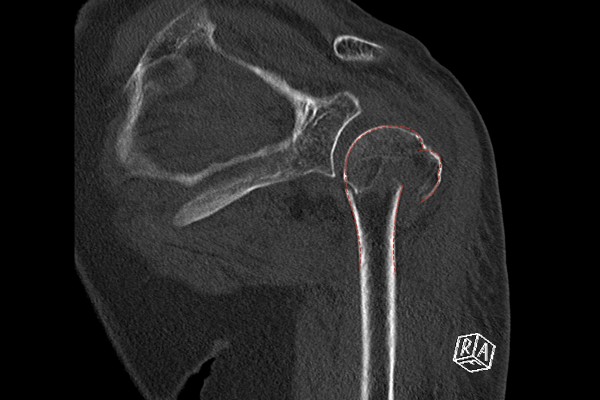

환자분께서 들고 오신 CT 사진에서도 어깨 3분위 골절이 확인되어 어깨 상완골 근위부 골절 (3분위 골절)(Fx. proximal humerus shoulder Lt (3 part))을 진단하였습니다.